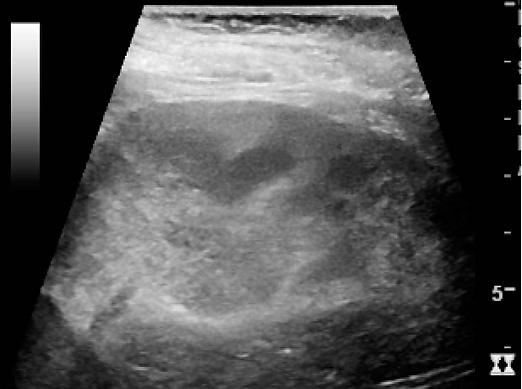

- ультразвуковое исследование (Ультразвуковое исследование) почек в фазе серозного воспаления при остром первичном пиелонефрите может не выявить патологических изменений в почках, в серозной фазе по УЗИ выявляется увеличение почек (или одной почки при одностороннем поражении) в размерах, уменьшение их подвижности при дыхании. При апостематозном пиелонефрите ультразвуковая картина такая же, как в фазе серозного воспаления (увеличение почек в размерах, ограничение их подвижности). Для карбункула почки при УЗИ характерно наличие гипоэхогенного участка без чётких контуров, иногда выбухание внешнего контура почки в этом месте. При формировании абсцесса почки при УЗИ определяется гипоэхогенный участок с чёткими контурами (капсула абсцесса) иногда с неоднородными анэхогенными участками в центре (жидкий гной). При выходе гнойного процесса за пределы капсулы почки (развитие паранефрита) при УЗИ определяется нечёткость паранефральной клетчатки с наличием в ней гипо- и анэхогенных компонентов.